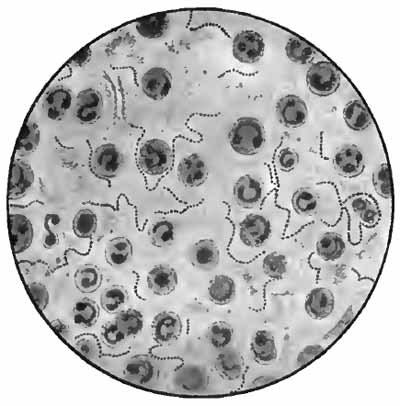

| FIG. 8.—Sputum from a case of actinomycosis; stained (Jakob). |

5. Actinomyces Bovis (Ray-fungus).—In the sputum of pulmonary actinomycosis and in the pus from actinomycotic lesions elsewhere small, yellowish, "sulphur" granules can be detected with the unaided eye. The fungus can be seen by crushing one of these granules between slide and cover, and examining with a low power. It consists of a network of threads having a more or less radial arrangement, those at the periphery presenting club-shaped extremities (Fig. 8). This organism, also called Streptothrix actinomyces, apparently stands midway between the bacteria and the molds. It stains by Gram's method.

[p. 32] Actinomycosis of the lung is rare. The clinical picture is that of tuberculosis.